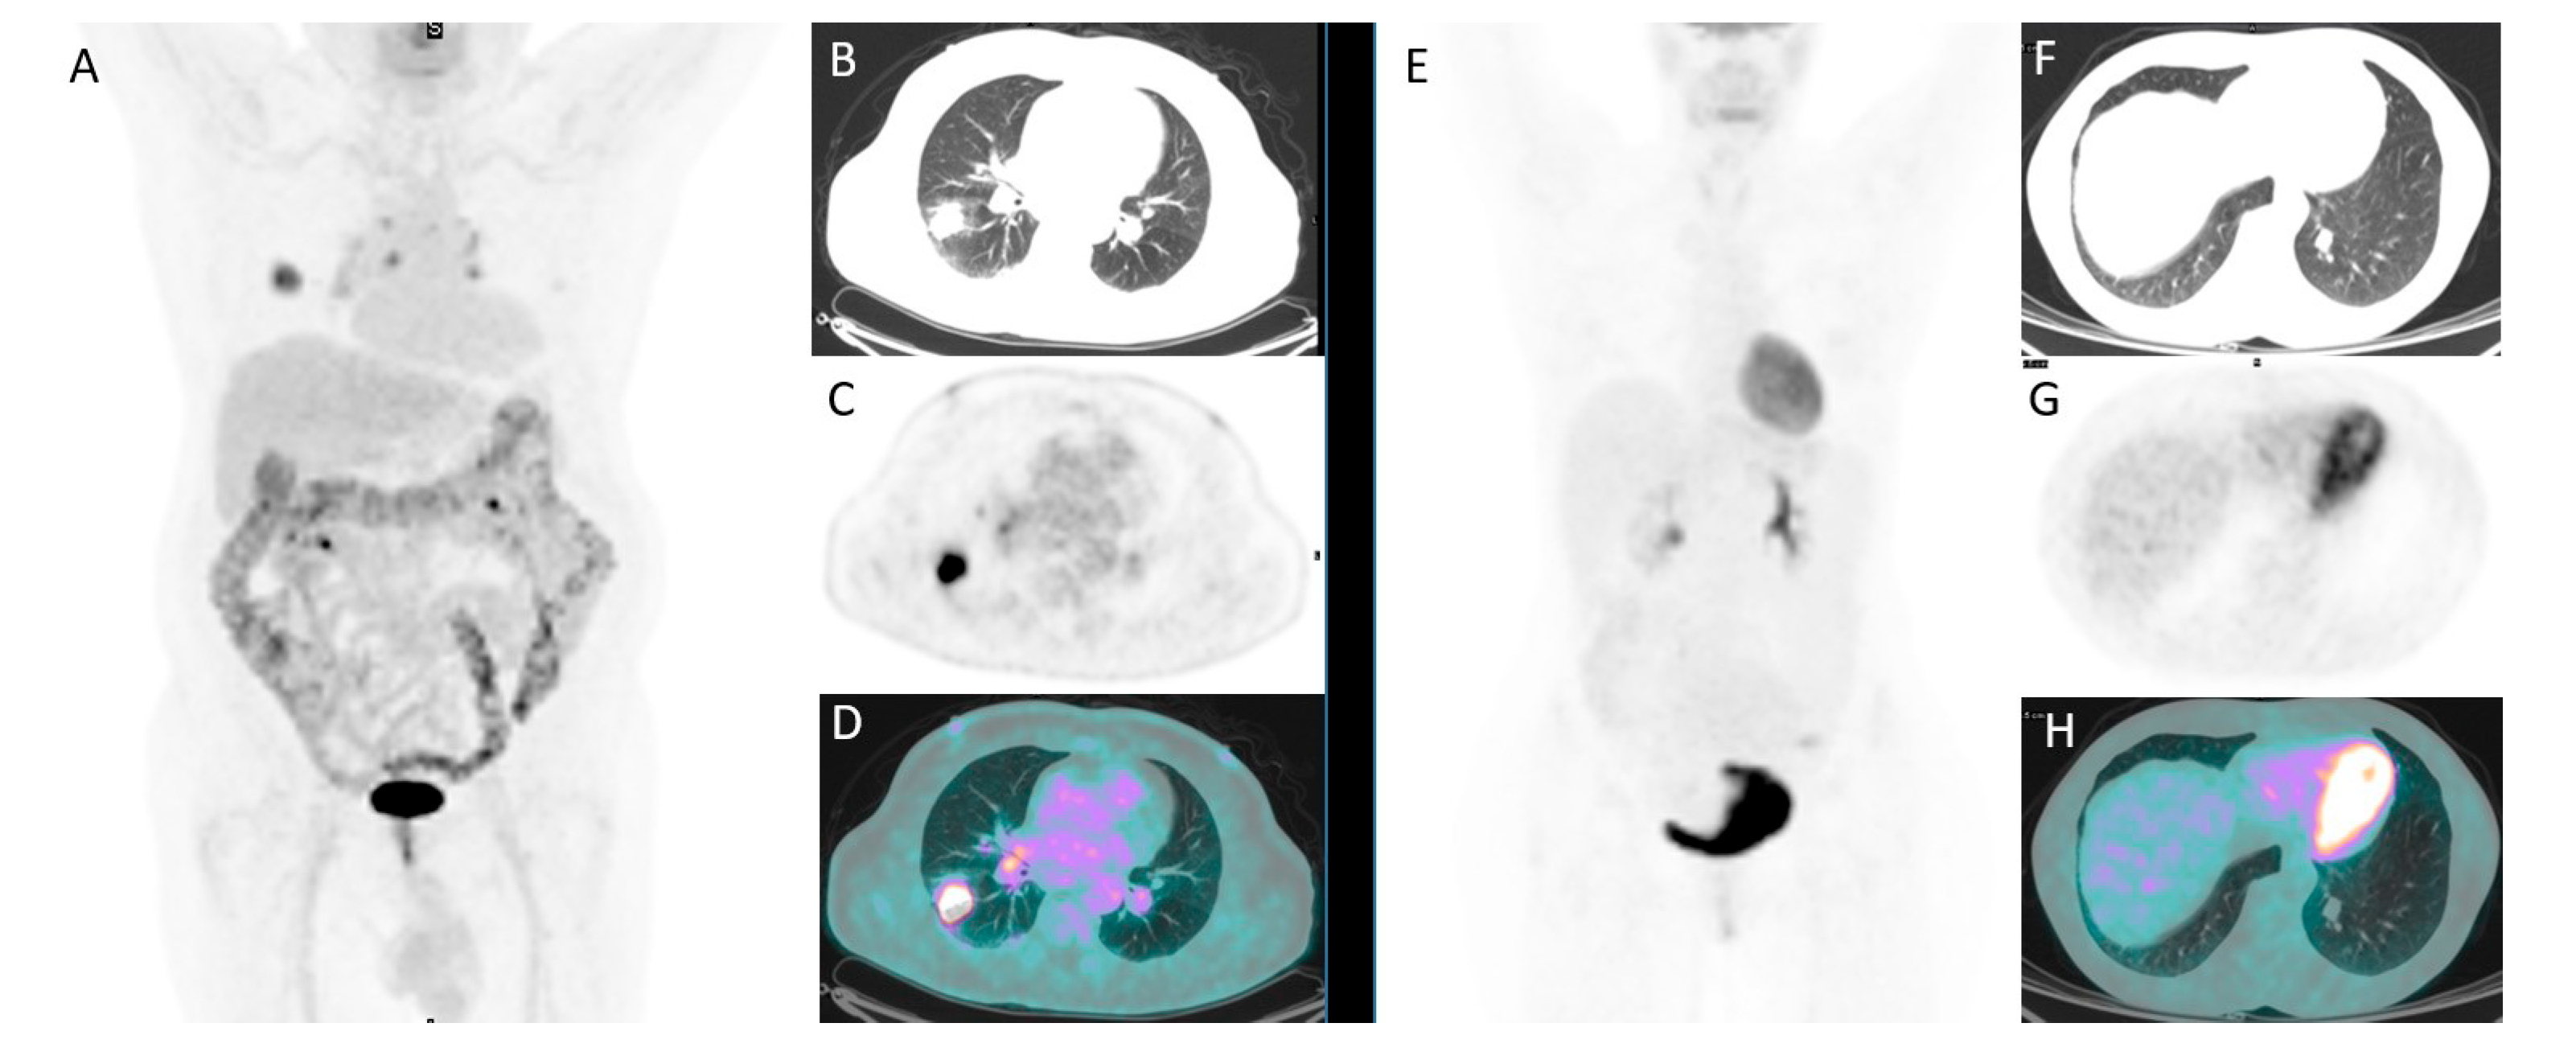

2.2. 18F-FDG PET/CT Imaging and Interpretation